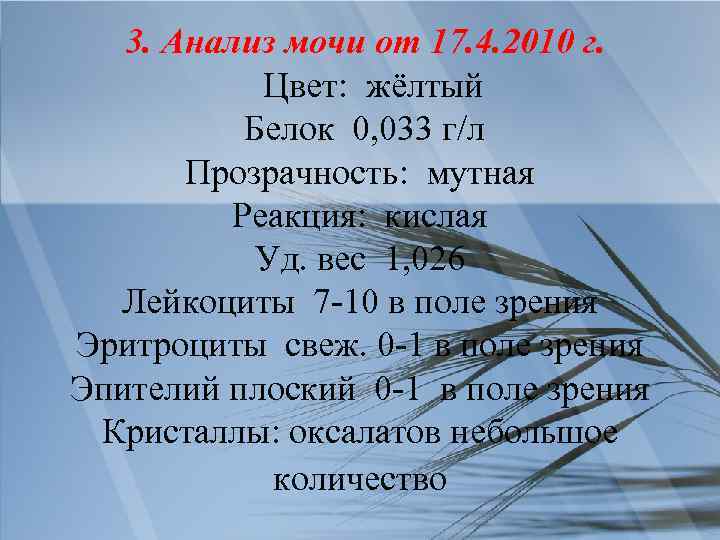

3. Анализ мочи от 17. 4. 2010 г. Цвет: жёлтый Белок 0, 033 г/л Прозрачность: мутная Реакция: кислая Уд. вес 1, 026 Лейкоциты 7 -10 в поле зрения Эритроциты свеж. 0 -1 в поле зрения Эпителий плоский 0 -1 в поле зрения Кристаллы: оксалатов небольшое количество